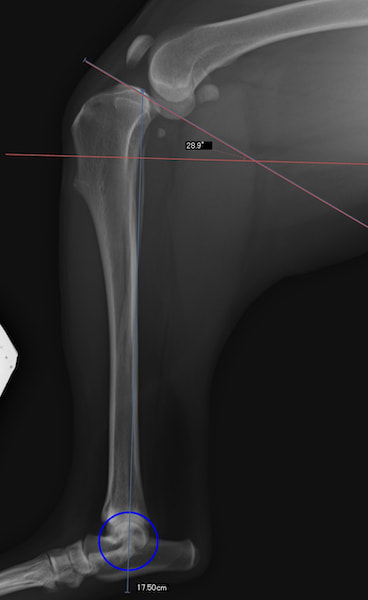

手術前後のTPA(脛骨高平部の角度)を測定しています。

約29°から約10°へ矯正されています。

手術前TPA 28.4° が術後TPA 11.7° に矯正されました。

術前TPA計測

術後TPA計測